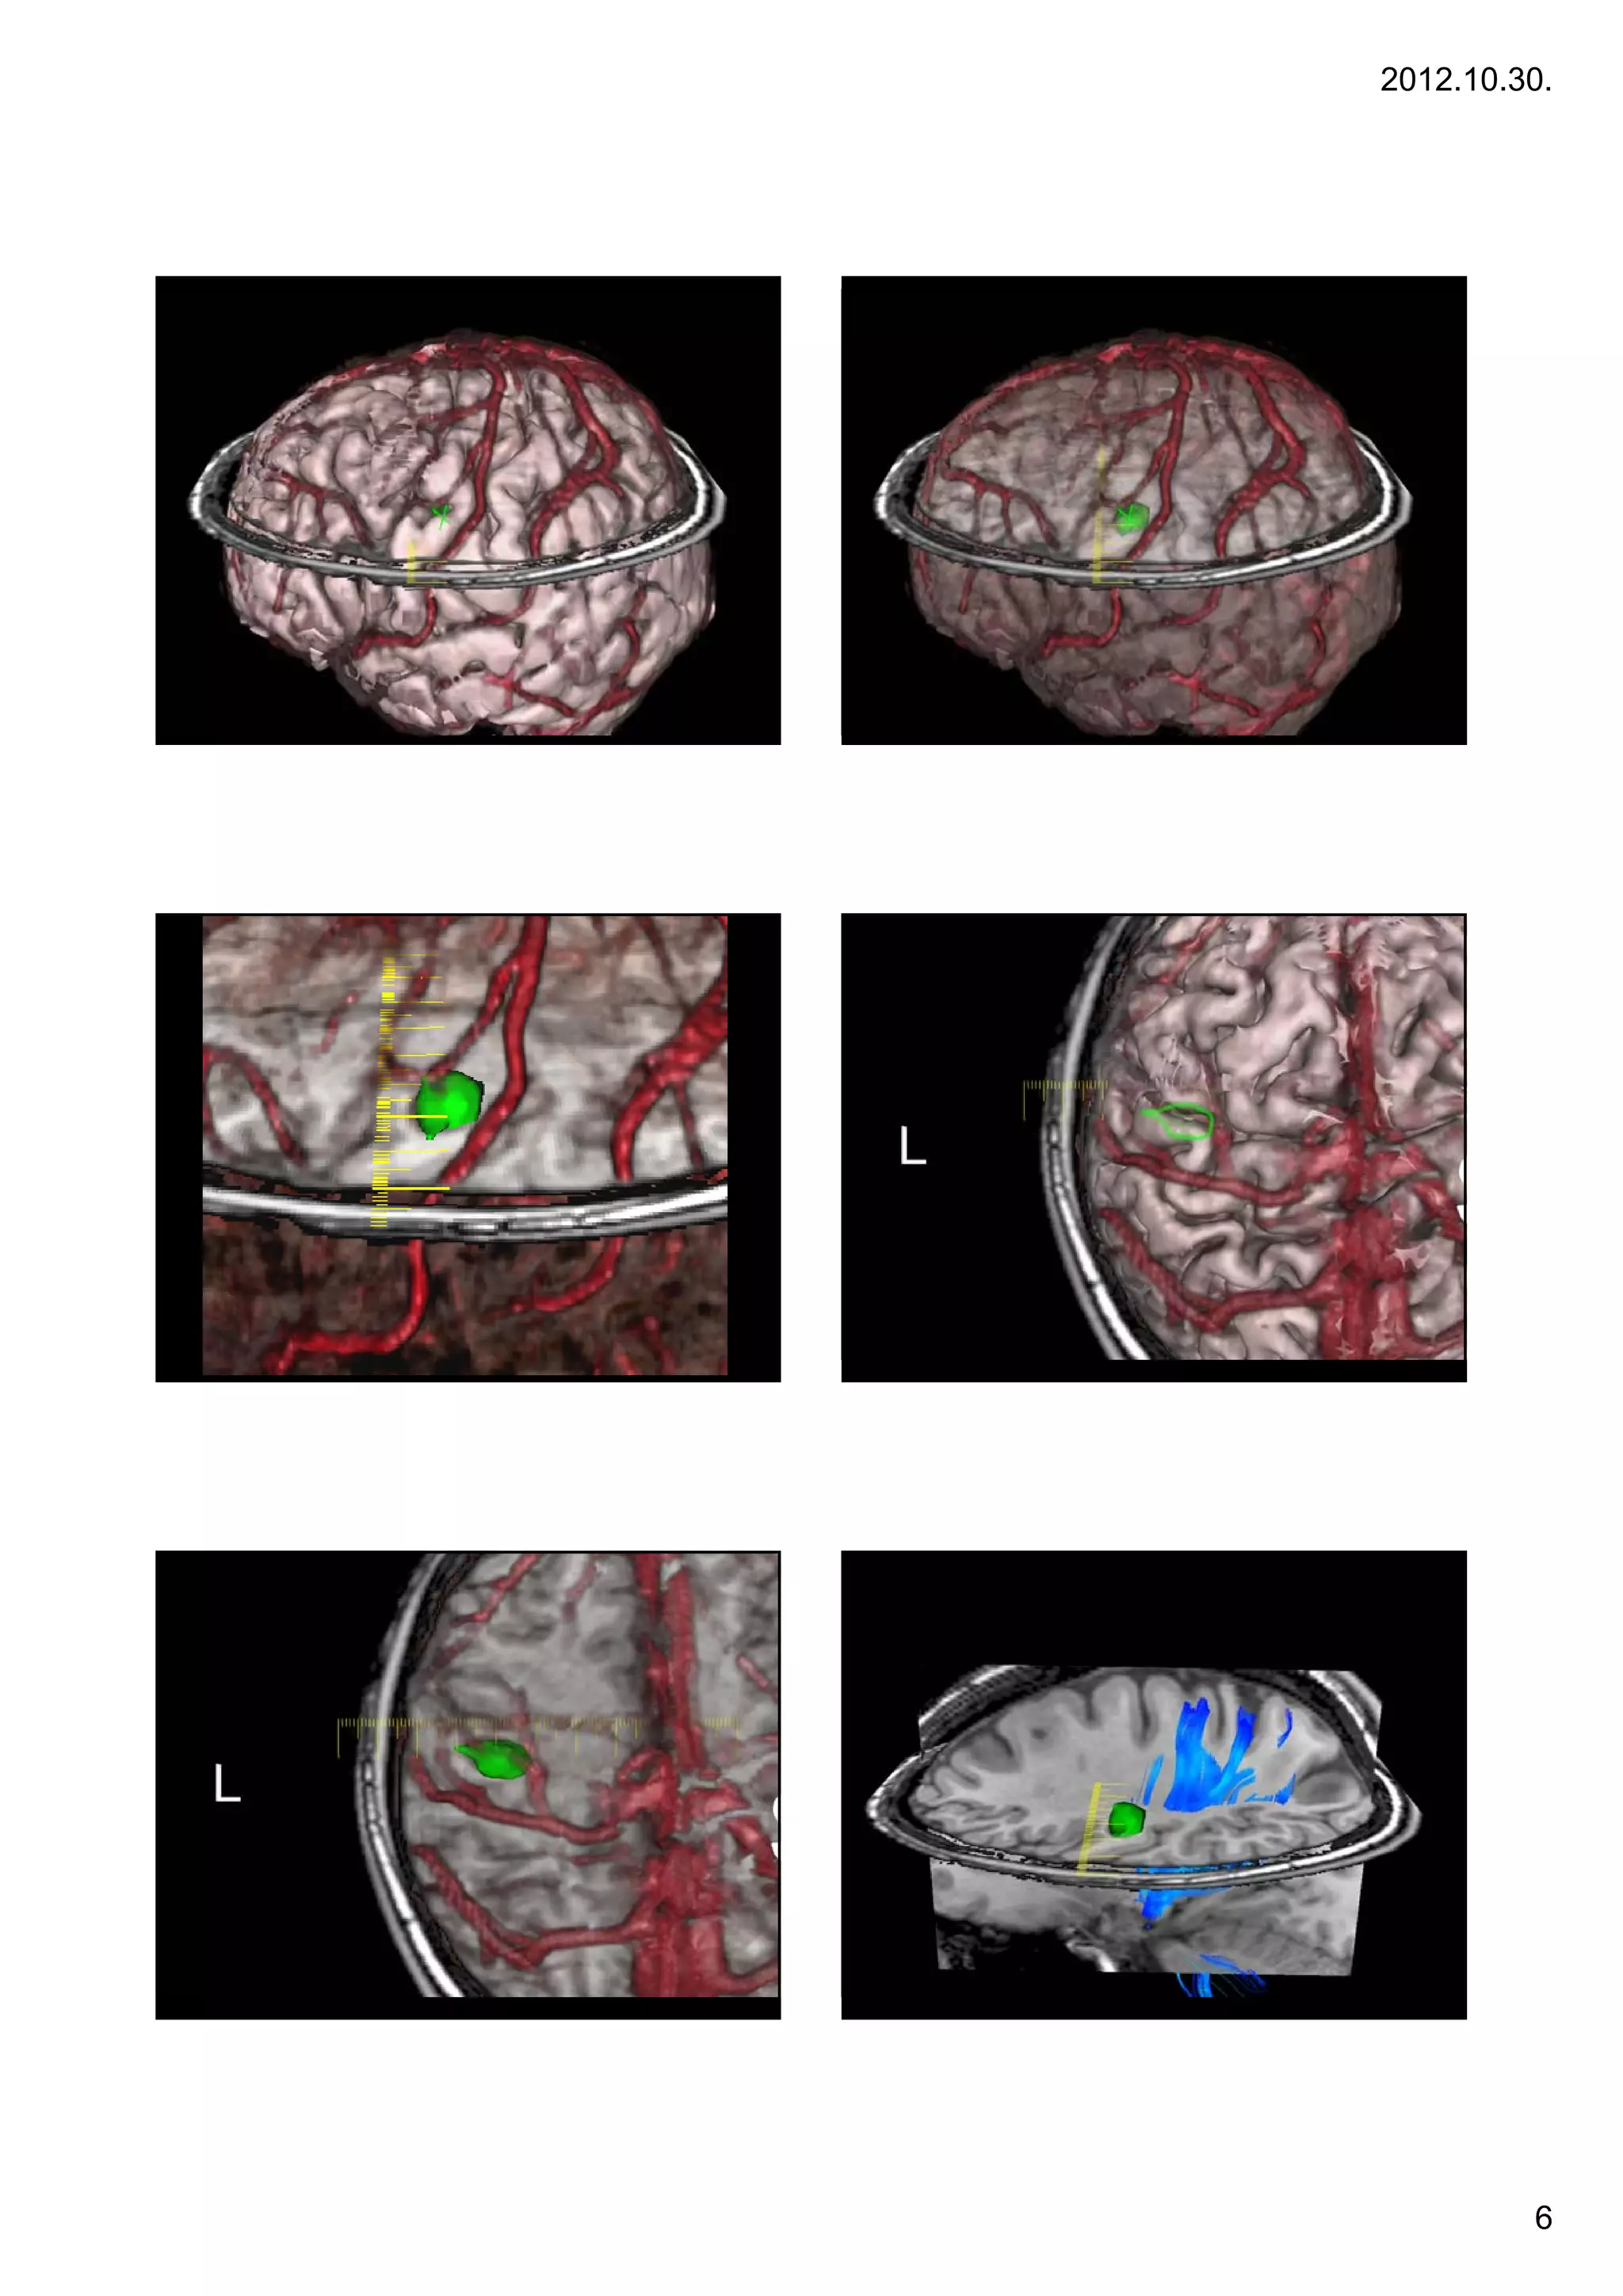

VISUALIZATION OF STRUCTURE

Recidive tumor, 2 foci, purple and magenta

Markers on the skin

removed temporal lobe parts

Case 6

6.

OPTIC RADIATION

CORTICOSPINAL TRACT

VISUALIZATION OF FIBERS